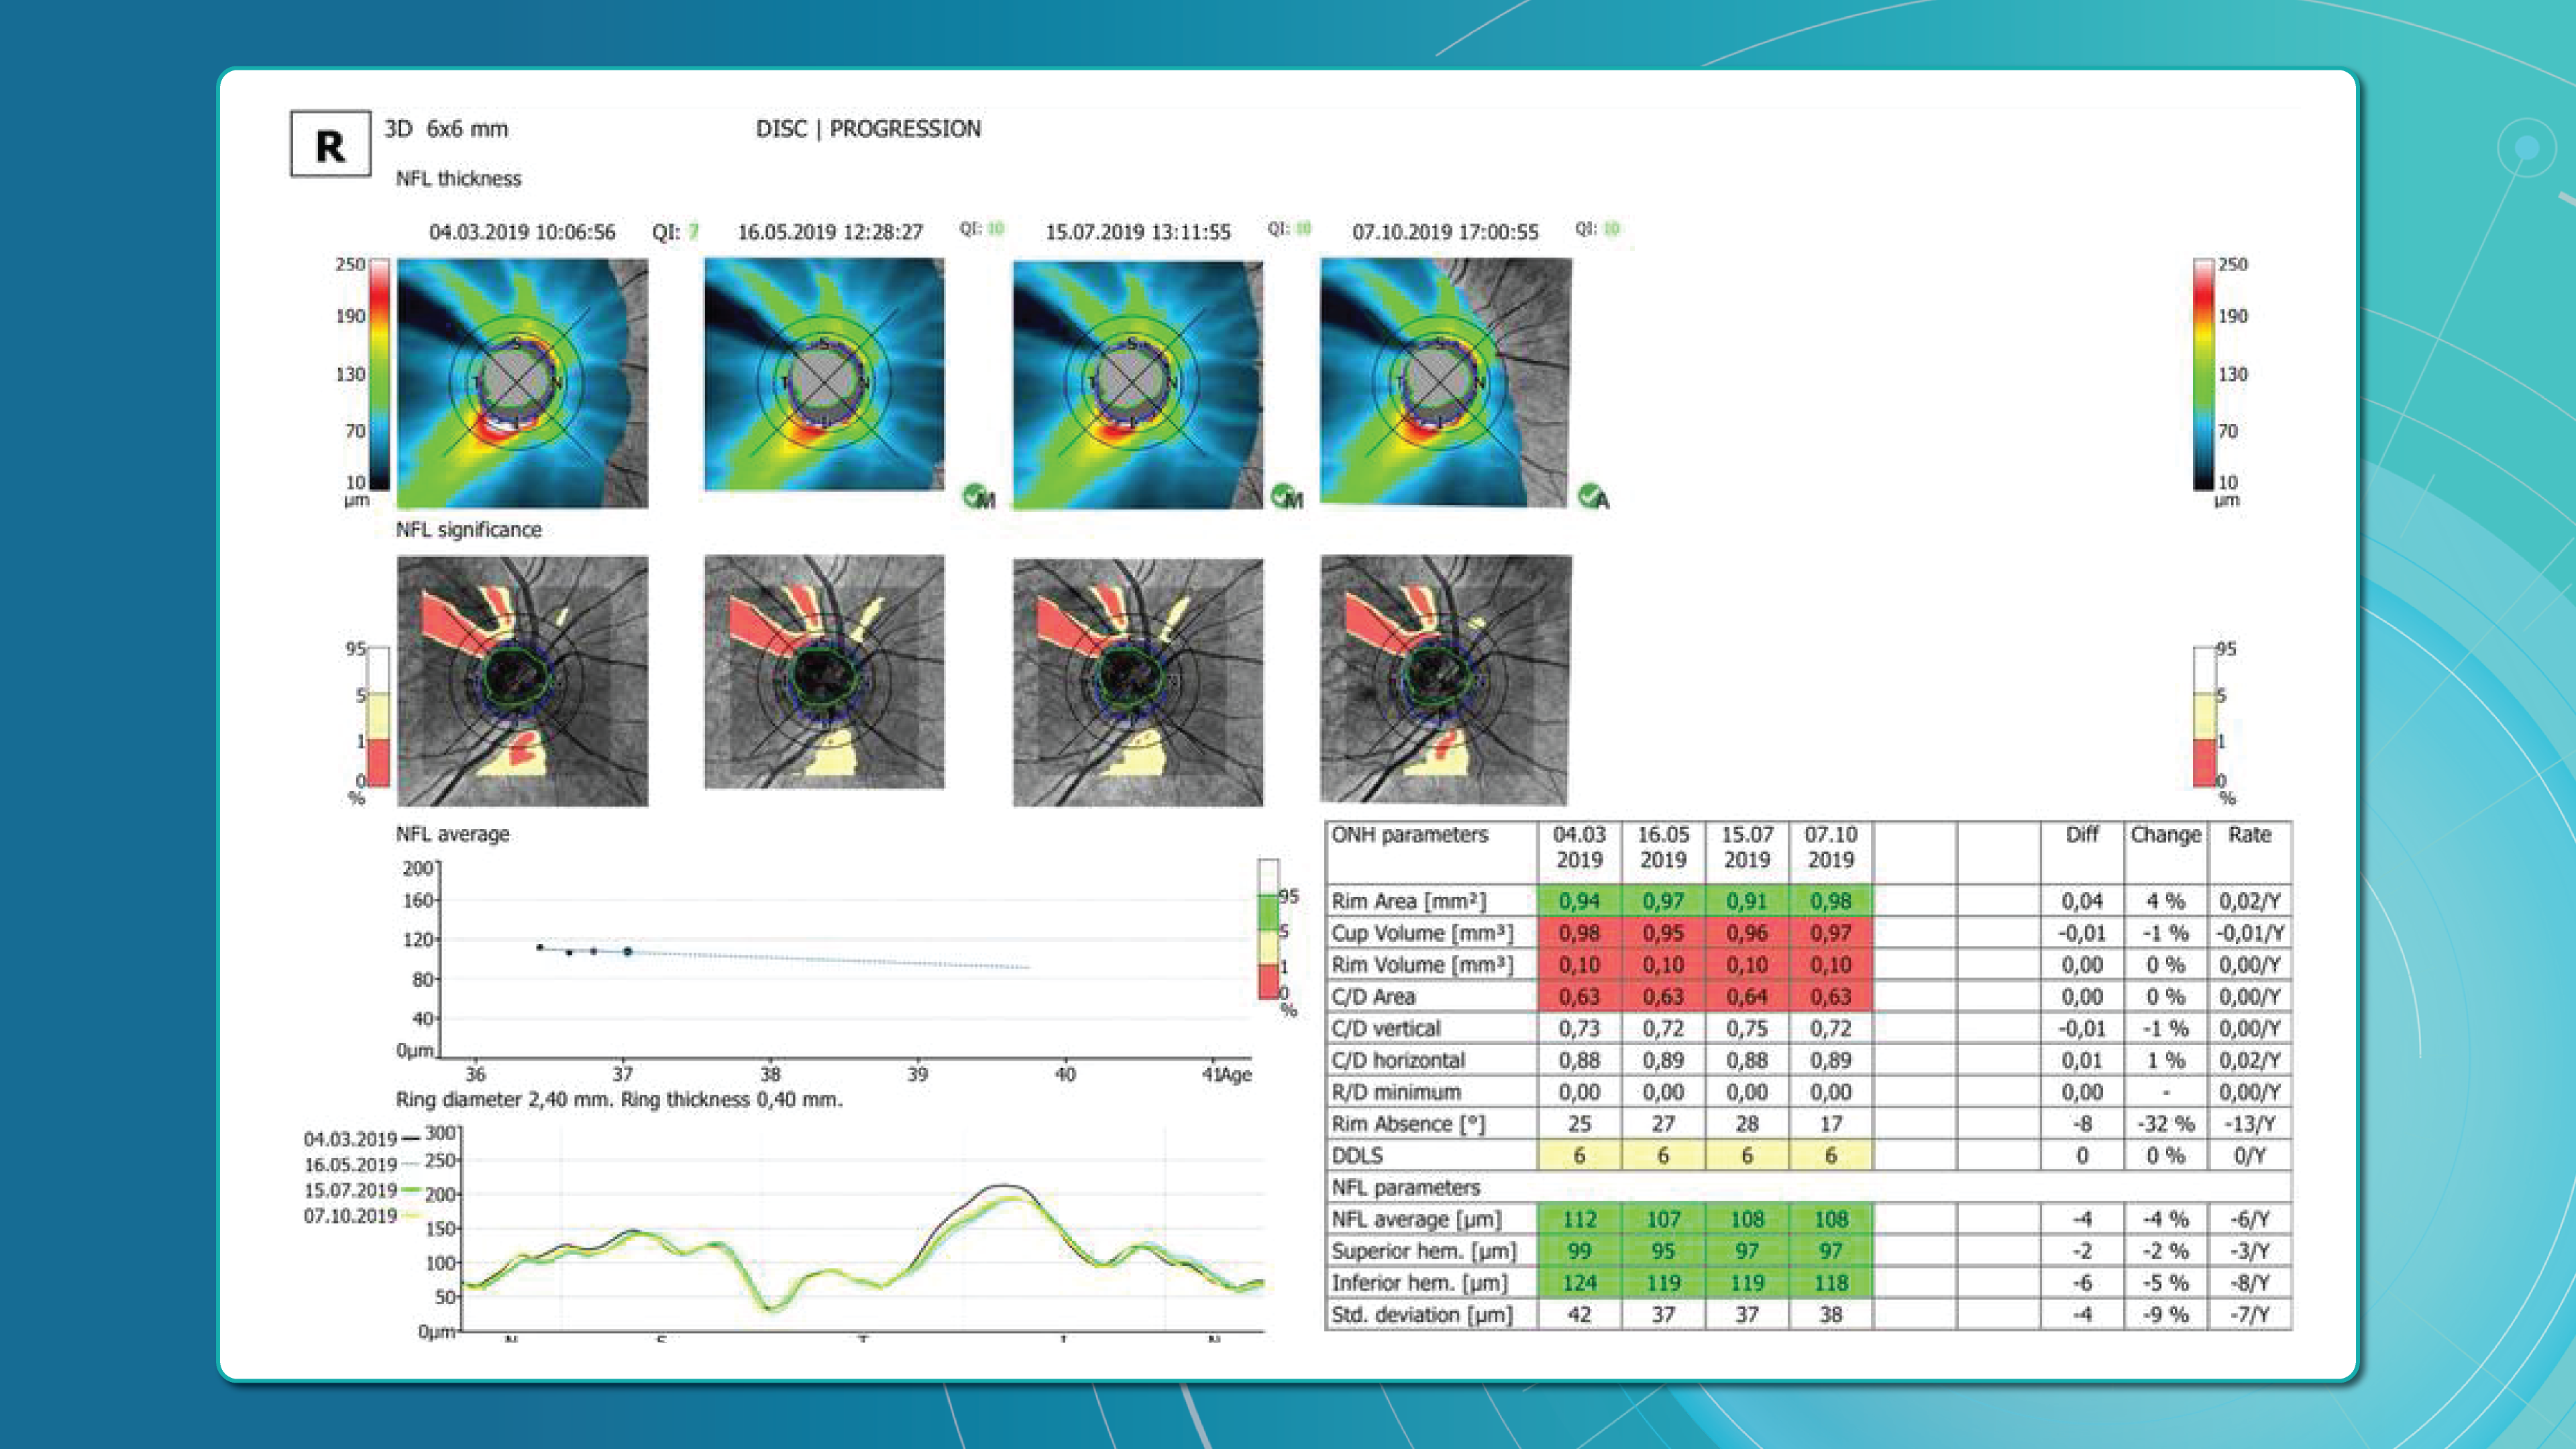

For instance, AI today can assess the early risk of glaucoma based on the GCC asymmetry measurements. Here is how AI-powered OCT workflow would look.

AI-assisted readings of OCT scans are already helping not only with pathology detection but also with the analysis of its progression or response to treatment. This represents a new approach to monitoring, where practitioners no longer need to sift through various patient notes but can directly compare reports from previous examinations and observe how, for instance, shadowing has changed in micrometers.

Measuring treatment progress: biomarkers tracking, pathology progression

Imaging biomarkers are a particularly attractive option for clinical practice due to their non-invasive and real-time nature. Quantitative measurements of retinal thickness, fluid volume, and other biomarkers relevant to diseases like diabetic retinopathy and age-related macular degeneration aid in treatment monitoring.

OCT reports with customized measurements and selected biomarkers, retinal layers, or segments allow for precise focus on treatment monitoring and patient response to therapy. This personalized approach enhances clinical decision-making by highlighting each case’s most relevant information.

In current clinical practice, macular damage assessment typically involves measuring the distance between the ILM and RPE layers, summarized in a post-scan report.

Subsequent follow-up visits will then display the most relevant picture, highlighting the most pertinent biomarkers for tracking a particular pathology (wet AMD in our example) and comparing their volume, progression, or regression through visits.

Millions risk irreversible vision loss due to undiagnosed glaucoma, underscoring the need for improved early detection. Current tests often rely on observing changes over time, delaying treatment assessment and hindering early identification of rapid disease progression. OCT frequently detects microscopic damage to ganglion cells and thinning across these layers before changes are noticeable through other tests. However, the earliest signs on the scan can still be invisible to the human eye.

AI algorithms offer insights into glaucoma detection by routinely analyzing the ganglion cell complex, measuring its thickness, and identifying any thinning or asymmetry to determine a patient’s glaucoma risk without additional clinician effort.